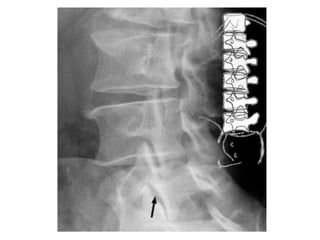

Rx

• Ap Laterales y oblicuas

• Grado de listesis (lateral)

• Perritos de Lachapelle (Oblicua)

Rx • Ap Lateralesy oblicuas • Grado de listesis (lateral) • Perritos de Lachapelle (Oblicua) 1. Hocico que es la apófisis transversa 2. Ojo, pedículo 3. Oreja, apófisis articular superior 4. Pata delantera, apófisis articular inferior 5. Rabo, lámina y apófisis articular superior del lado opuesto 6. Pata trasera, apófisis articular inferior lado opuesto 7. Cuerpo, lámina